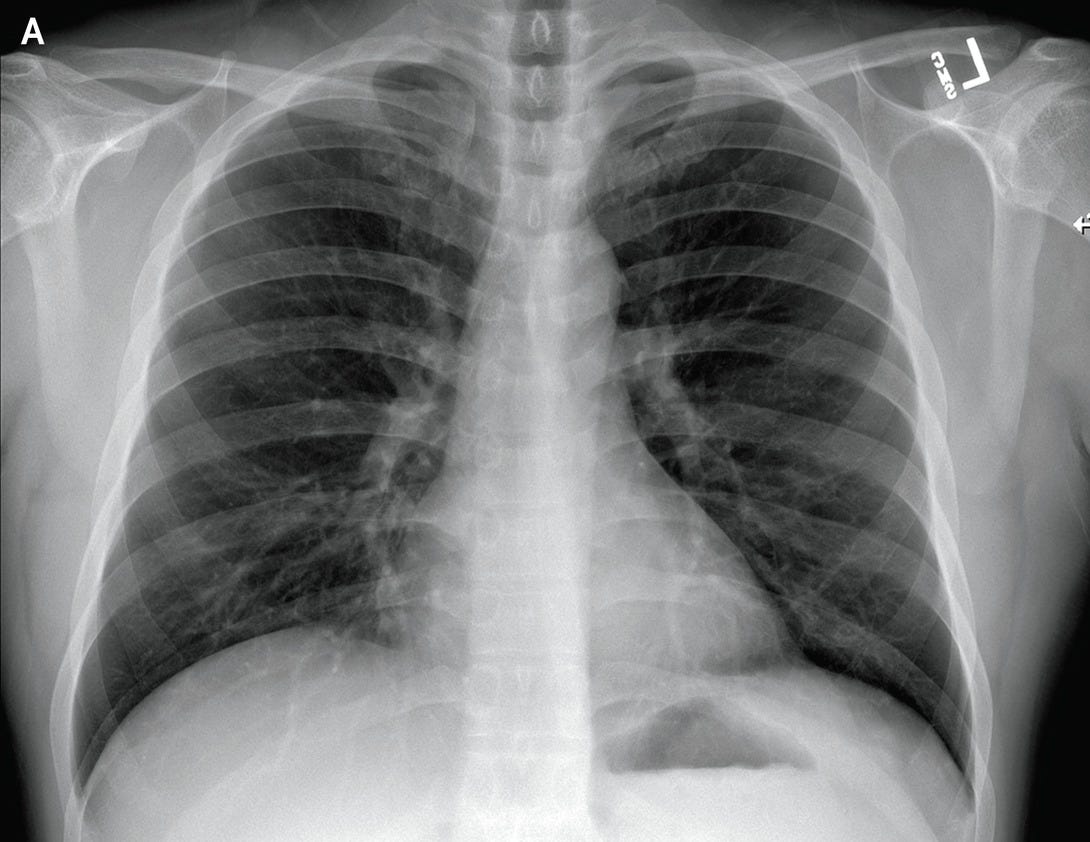

In our experience, baseline cxr had a sensitivity of 68.1%. It is mentioned that this dataset is continuously updated. The dataset is provided along with the tool so that researchers, or anyone who wants to play, can explore and modify it.

This dataset contains 3 types of images: This other repository in kaggle we have also taken into account: The proposed approach selected successfully 130 and 86.